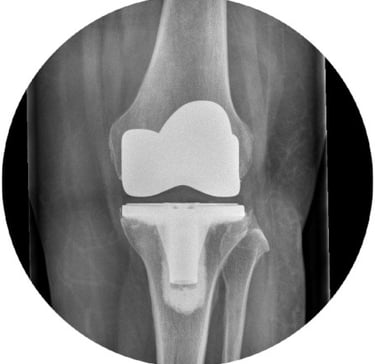

Knee Replacements:

Mr Pang performs his total knee replacements using the latest robotic assisted system to ensure optimal positioning of the prosthesis. He is also trained to perform robotic-assisted partial knee replacements.

He has experience in revision knee surgery and is adept in using megaprosthesis in more complex cases.